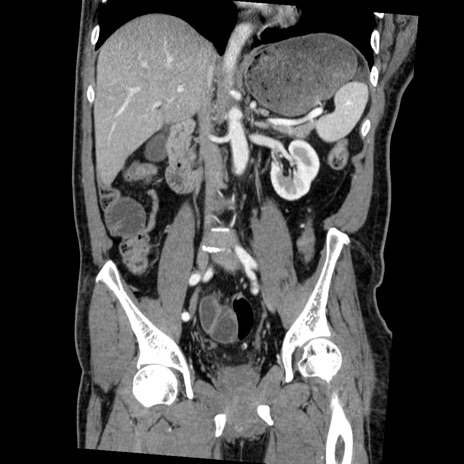

横断像

【症例】50歳代男性

【主訴】腹痛

【現病歴】AVMからの被殻出血のため回復期リハ病棟入院中。 本日午後3時頃急に下腹部痛が出現した。

【既往歴】AVM、被殻出血、虫垂炎、高血圧

【身体所見】意識晴明、左半身不全麻痺、会話の理解は良好、36.5°C、腹部:膨隆、全体に板状硬、下腹部正中に圧痛点あり、反跳痛-、筋性防御不明、右下腹部にope scar

【データ】WBC 9400、CRP 0.06